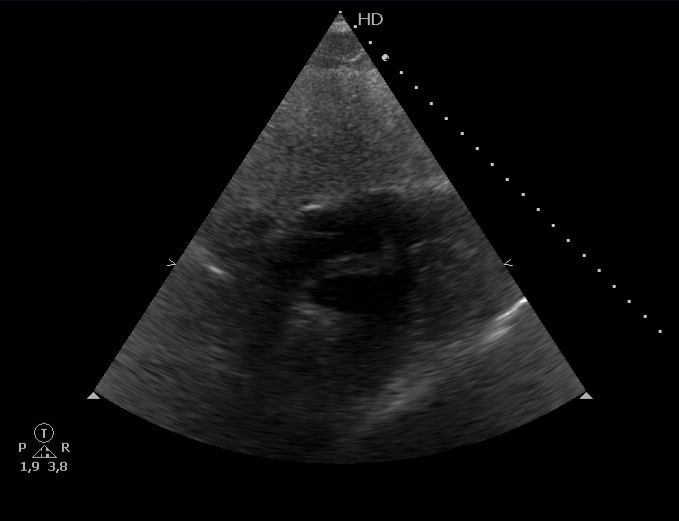

Escalas de riesgo probable para tromboembolismo pulmonar, cursando prueba de imagen que confirma patología y ampliando estudio con ecografía cardíaca que muestra presencia de émbolo intracardíaco.

Signos de disfunción del VD en el momento inicial, y mayor riesgo de muerte prematura.

Clasificación de trombo intracardíaco en Tipo A, B o C; el A tiene forma de gusano o serpiente, es móvil y suele asociarse a TVP.